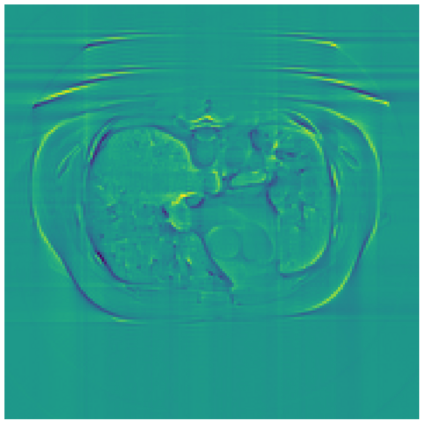

Sparse-view computed tomography (CT) -- using a small number of projections for tomographic reconstruction -- enables much lower radiation dose to patients and accelerated data acquisition. The reconstructed images, however, suffer from strong artifacts, greatly limiting their diagnostic value. Current trends for sparse-view CT turn to the raw data for better information recovery. The resultant dual-domain methods, nonetheless, suffer from secondary artifacts, especially in ultra-sparse view scenarios, and their generalization to other scanners/protocols is greatly limited. A crucial question arises: have the image post-processing methods reached the limit? Our answer is not yet. In this paper, we stick to image post-processing methods due to great flexibility and propose global representation (GloRe) distillation framework for sparse-view CT, termed GloReDi. First, we propose to learn GloRe with Fourier convolution, so each element in GloRe has an image-wide receptive field. Second, unlike methods that only use the full-view images for supervision, we propose to distill GloRe from intermediate-view reconstructed images that are readily available but not explored in previous literature. The success of GloRe distillation is attributed to two key components: representation directional distillation to align the GloRe directions, and band-pass-specific contrastive distillation to gain clinically important details. Extensive experiments demonstrate the superiority of the proposed GloReDi over the state-of-the-art methods, including dual-domain ones. The source code is available at https://github.com/longzilicart/GloReDi.